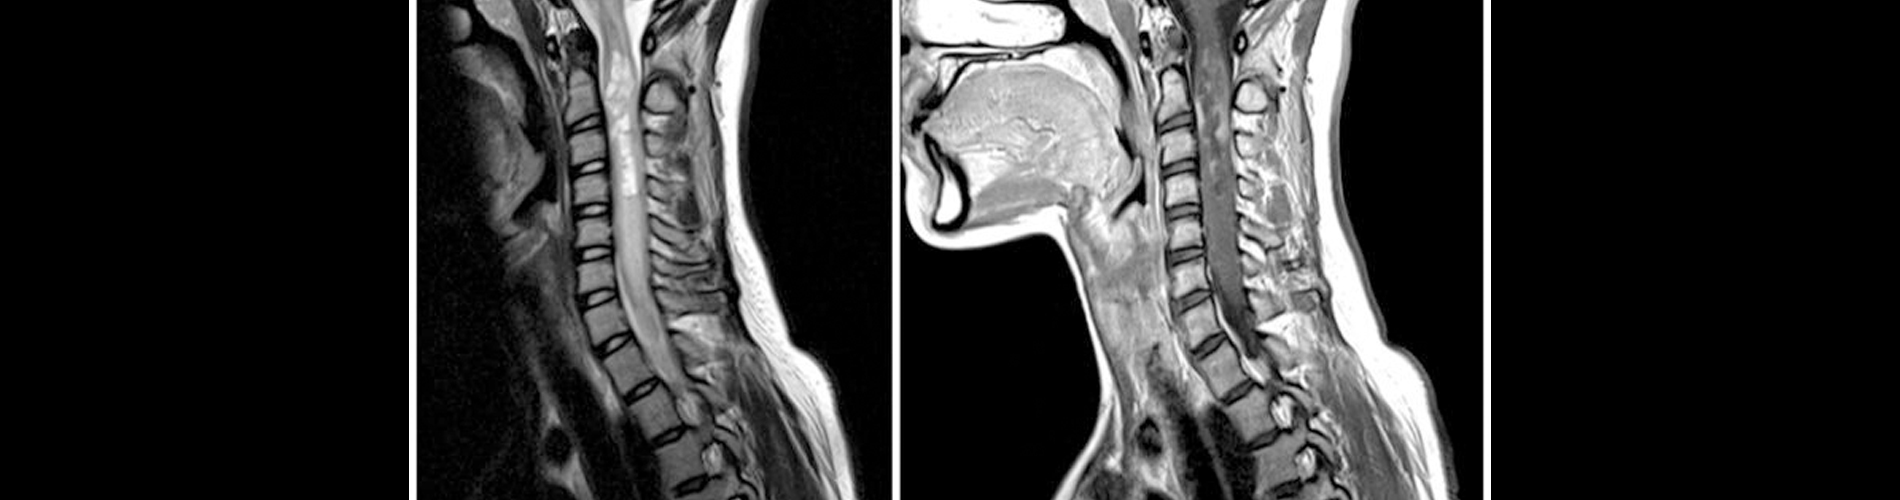

Servikal MR, boyun bölgesindeki (servikal omurga) yapıları, sinirleri, omurilik dokusunu ve çevresindeki yumuşak dokuları incelemek için kullanılan bir görüntüleme yöntemidir. Radyasyon içermeyen ve non-invaziv bir yöntem olması nedeniyle güvenli ve sık tercih edilen bir tekniktir.

Servikal MR Nedir?

• Odak Alanı: Boyun omurları (C1-C7), omurilik, sinir kökleri, diskler, bağlar ve çevre dokular.

• Teknoloji: Manyetik alan ve radyo dalgaları kullanarak yüksek çözünürlükte kesit görüntüler elde edilir.

Servikal MR, boyun bölgesindeki omurga, omurilik ve çevre dokuların detaylı olarak incelenmesini sağlar. Boyun ağrıları, fıtık, tümör, enfeksiyon veya travma gibi birçok hastalığın teşhisinde önemli bir rol oynar. Doktorunuzun yönlendirmesiyle yapıldığında güvenli ve etkili bir tanı yöntemidir.